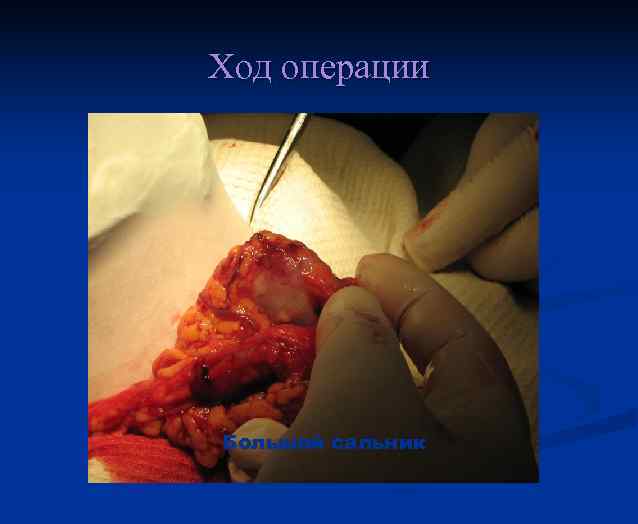

Ход операции Большой сальник

Ход операции Большой сальник